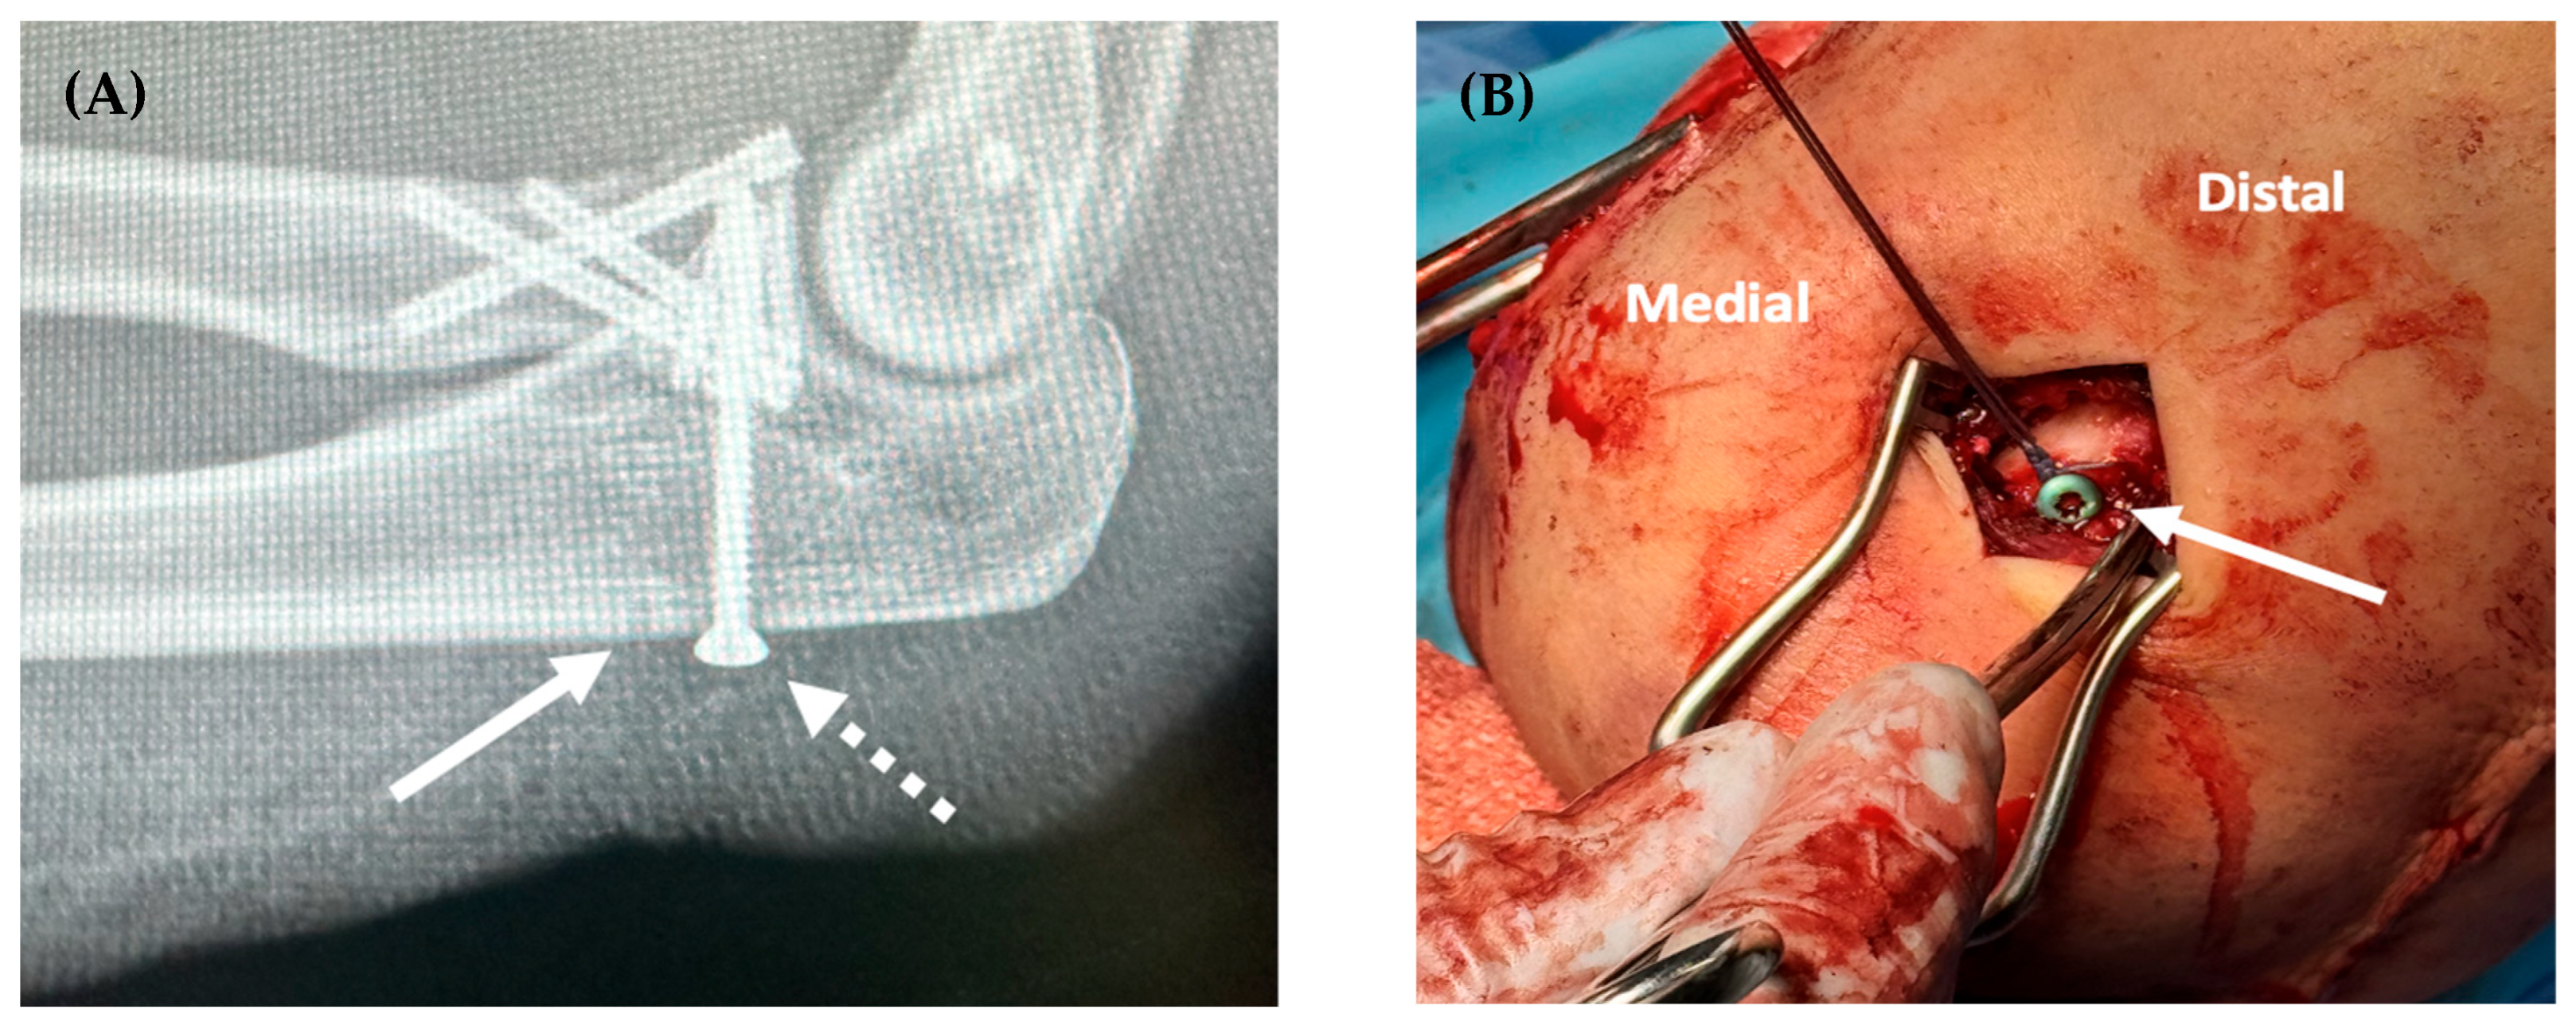

In an effort to improve the strength of suture fixation, other methods have been developed that incorporate small anchoring devices. Cortical button fixation is one strategy that has been effectively utilized in other areas of orthopaedic surgery. A similar technique, the “screw post” construct, secures the suture limbs to a cortical screw placed in the proximal ulna. For this construct, the cortical screw can be placed independently, acting solely as a post, or serve as a secondary method of fixation for a large coronoid fragment. This technique has been effective in the management of ligamentous reconstructions, such as those of the anterior cruciate ligament (ACL) [6,7]. The purpose of this study was to compare the biomechanical strengths of three different techniques for anterior capsule and coronoid fixation: bone tunnel, screw-post construct (Figure 1), and cortical suture button (Figure 2).

Figure 1. Lateral elbow radiograph demonstrating coronoid fixation with a 3.5 mm screw (dashed arrow) and the 2 mm drill tunnel used to pass the non-absorbable suture securing the anterior capsule (solid arrow, (A)). The screw was used as post to secure the suture and capsule (B).